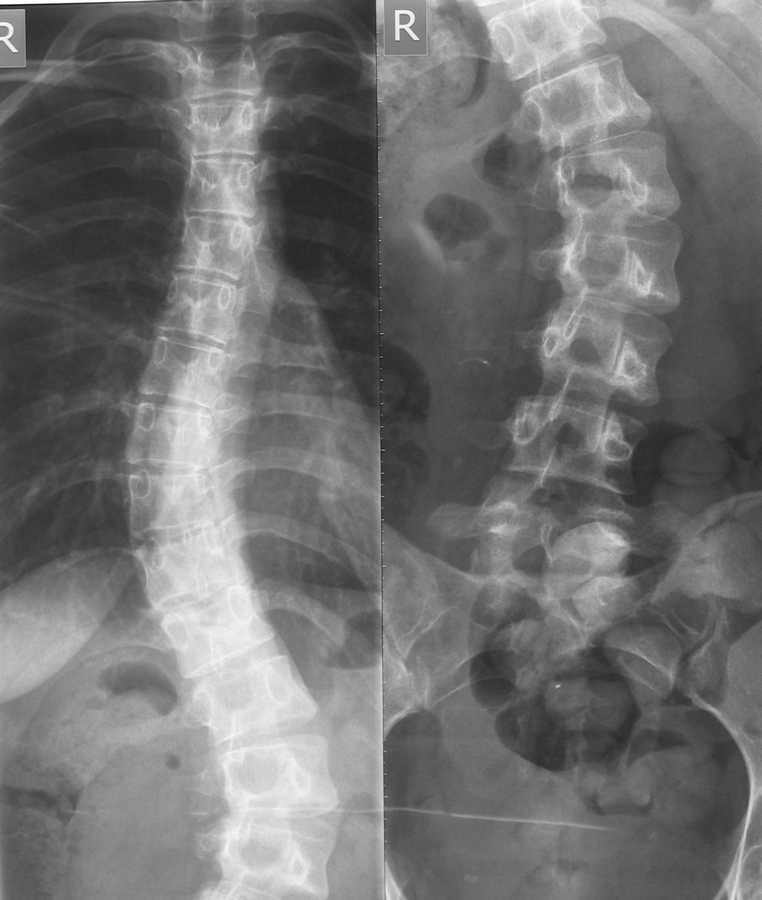

Здравствуйте уважаемые коллеги. Помогите разобраться в ситуации. Девушка 22 года, впервые выявлен сколиоз около 5 лет назад.

Получала несколько раз курс консервативного лечения. На данный момент ситуация видна на представленном снимке. Клинически проявляется только в косметическом дефекте, боли не беспокоят. имеет ли смысл устранять косметический дефект хирургически,если - да, то на какой базе?

С некоторым домысливанием можно сказать, что у пациентки имеется:

1. Компенсированный (сбалансированный) сколиоз

(лордо? кифо?сколиоз – нет боковых снимков)

2. D25°-S29°

3. Кинг-I?(нет функциональных снимков)

4. Риссер-5

5. Таннер Т5-P5

6. Рост пациентки - ?

7. Болевого синдрома, выраженных дегенеративных изменений в позвоночнике нет

Деформация типа кинг I c выраженным искривлением поясничного отдела, ротацией поясничных позвонков, клиновидной деформацией L1,4,5, требует включение в спондилодез как минимум L4 позвонка для сохранения баланса туловища. Верхний уровнень спондилодеза ориетировочно Т5.

Вентральная мобилизация и передний спондилодез в даном случае не показаны.

Добавит ли косметичности разрез по всей спине, можете ли вы прогнозировать отстутствие хронического болевого синдрома и осложненйи. связанных с операцией. Думаю нет, поэтому считаю оперативное лечение не показанным.